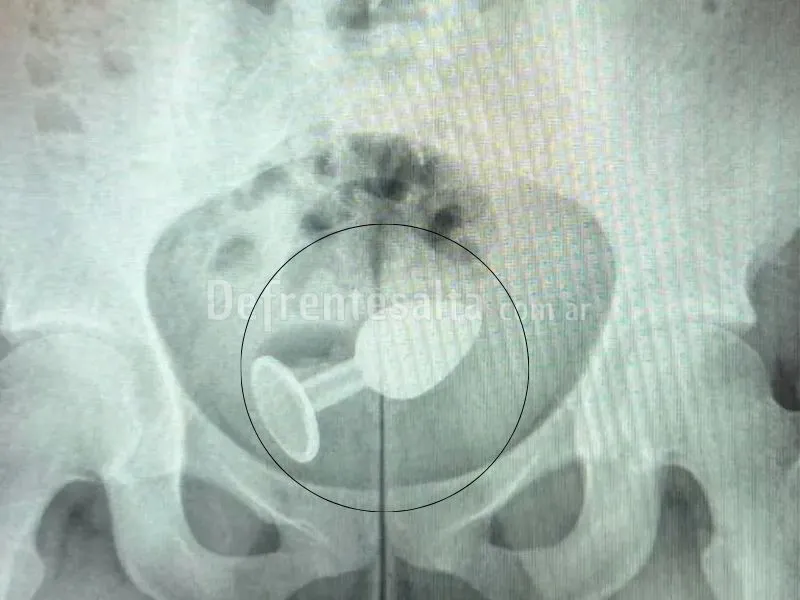

Una mujer tuvo que recibir asistencia médica tras sufrir un accidente con un juguete sexual. En este caso, la mujer se había colocado un plug anal, pero en medio del acto sexual el juguete le provocó una grave herida. Tras el mal momento, fue de inmediato a una guardia médica.

La mujer fue atendida por el doctor Daniel Brosco, cirujano coloproctólogo, quién le realizó una radiografía en la cual se puede observar con claridad el juguete sexual dentro de su cuerpo. Como consecuencia, la paciente tuvo que ser internada para que puedan extirpárselo, aunque no requirió cirugía.